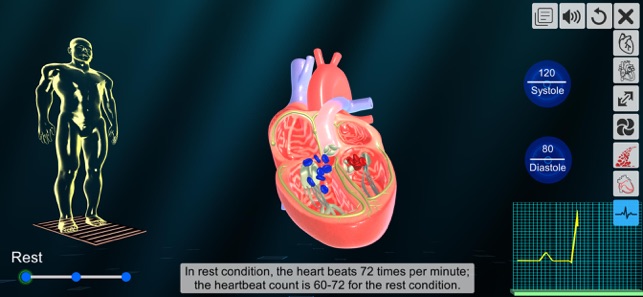

7. ECG of heart

The app ‘Heart - An incredible pump’ also updates the health conscious users to ascertain the variation in the heart rate with the kind of physical activity by exploring the ‘ECG’ section.